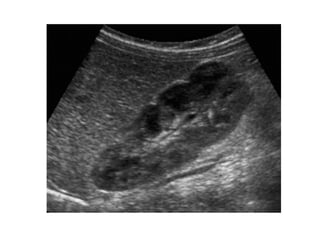

Foetale lobuatie Embryologisch bestond de nier uit meerdere lobules die fuseren en groeien. Foetale lobualatie,incomplete fusie van de renale lobules, wordt soms gezien bij volwassenen.  US/CT/MR: gladde indentaties van niercortex  tussen  de pyramides.  DD corticale scarring. Dit wordt gezien thv de pyramiden.

Foetale lobuatie Embryologischbestond de nier uit meerdere lobules die fuseren en groeien. Foetale lobualatie,incomplete fusie van de renale lobules, wordt soms gezien bij volwassenen. US/CT/MR: gladde indentaties van niercortex tussen de pyramides. DD corticale scarring. Dit wordt gezien thv de pyramiden.